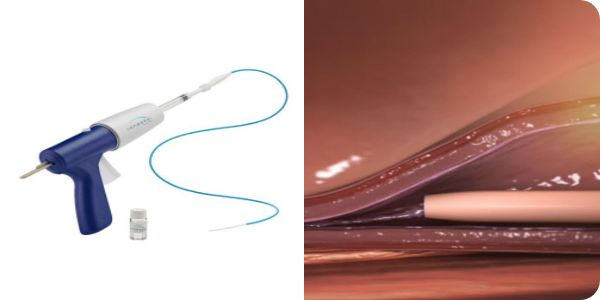

基本的には皮膚に注射をして行うため、皮膚を切る必要がありません。カテーテルから高周波で熱を発生させ行います。

- ※画像の無断転用は禁止です

血管内焼灼術と同様、皮膚を切る必要がありません。

カテーテルから瞬間接着材(シアノアクリレート)を血管内に注入します。

- シアノアクリレート系薬剤アレルギー(まつ毛エクステンション、付け爪、カツラ接着 など)

- シックハウス症候群

- 膠原病、一部のアレルギー疾患を有する方には適しません。

- ※画像の無断転用は禁止です